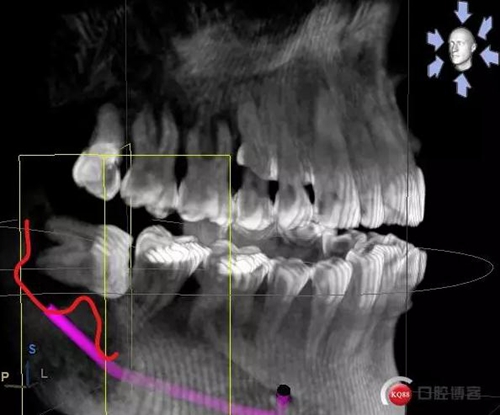

X線及CBCT檢查:47、48根尖周區(qū)大面積低密度影像,波及下牙槽神經(jīng)管,部分區(qū)域至神經(jīng)管以下。CBCT顯示神經(jīng)管走形于47根尖炎癥區(qū)下方(已侵犯)48炎癥區(qū)頰側(cè)(已侵犯)

術(shù)前CBCT分析

術(shù)后影像分析

對于曲面斷層片的分析,當(dāng)智齒埋伏牙的根尖與下牙槽神經(jīng)有重疊影像時(shí),常常可采用觀察重疊部分牙根的牙周膜和硬骨板是否連續(xù),下頜管是否比牙根密度高,下頜管是否變窄等,來辨別牙根與神經(jīng)管的位置關(guān)系。當(dāng)然曲面斷層片也很難避免其失真變形的自身局限性。拍攝CBCT能更為直觀預(yù)估其風(fēng)險(xiǎn)。但切記盲目的嘗試和挑戰(zhàn)。